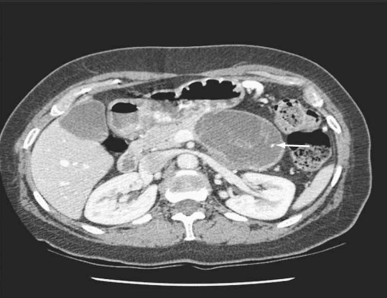

Mulher de 39 anos procurou atendimento por dor abdominal vaga, de fraca intensidade, há 4 meses. No exame físico, detectou-se uma massa abdominal de limites imprecisos e pouco dolorosa. Foi solicitada tomografia abdominal (imagem demonstrada). O exame histológico do material colhido por punção aspirativa com agulha fina revelou níveis baixos de amilase, presença de células ricas em mucina e estroma similar ao do ovário. O diagnóstico da paciente é:

(TOWNSEND JR., C. M.; BEAUCHAMP, R.D.; B. EVERS, M. AND MATTOX, K.L. SABISTON - Tratado de Cirurgia. 20ª Edição, Ed. Elsevier, 2019, Cap. 55, pg. 2395)